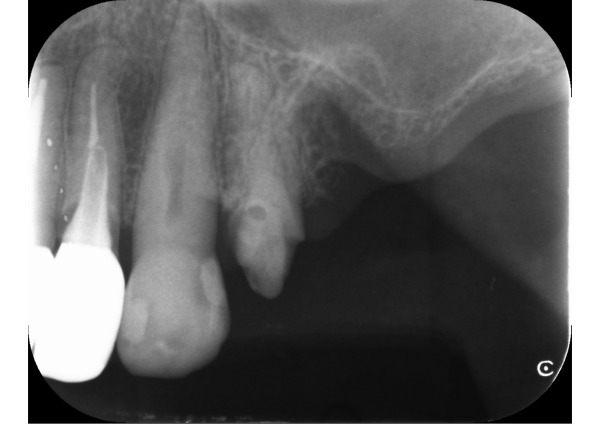

まずエックス線検査をおこなったところ、左上5番が割れていたため、保存ができない状態であることがわかりました。また、左上4番は残すことができても、差し歯にするほど歯の高さは残っていませんでした。